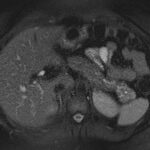

Mujer de 36 años que ingresa a Hospital Sanatorio Franchin el 11 de octubre de 2023 de forma programada para realización de duodeno pancreatectomía cefálica por tumor de cabeza de páncreas en estudio. Refiere hallazgo de lesión en forma incidental durante estudio de control hace dos meses por presentar antecedentes familiares (neoplasia endocrina múltiple). Se interna para manejo quirúrgico. Estudios de tomografía revelan formación nodular localizada en cabeza y cuerpo pancreático de paredes gruesas que mide 24 x 28 mm, que en resonancia se muestra hiperintensa en T2 y realce periférico luego de la administración de contraste endovenoso. Presenta restricción en la difusión con caída de la señal ADC, por lo que se vincula con una lesión de alta celularidad.